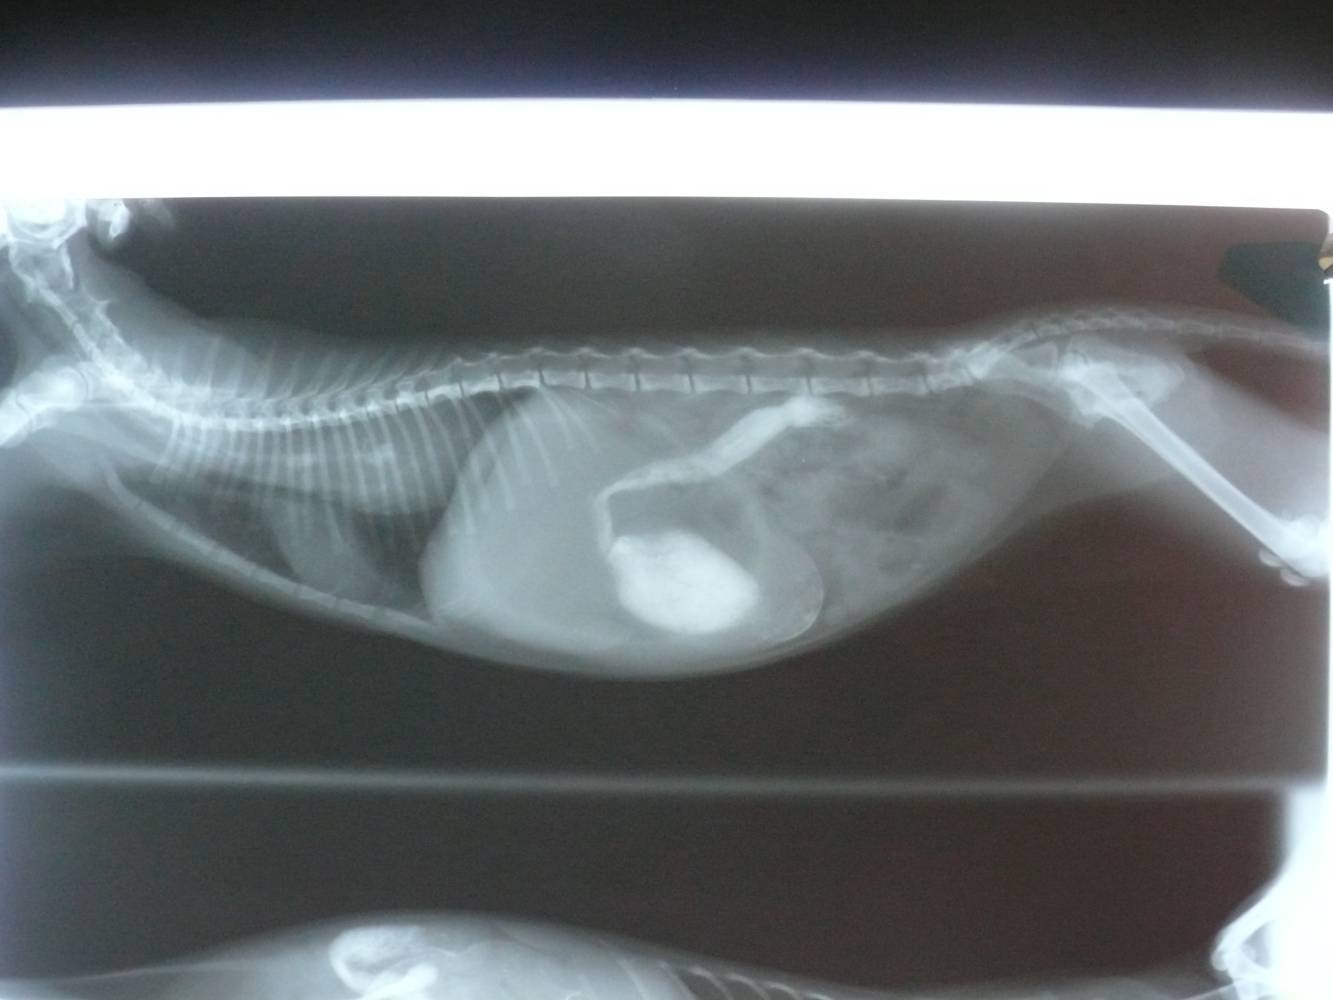

的醫助,到院後,發現貓很喘,嘴巴又都是血,先照X光,初步發現是助骨

斷了,胸腔出血,呼吸有困難,先住院,並提供氧氣,讓貓呼吸能順暢一點

,斷掉的肋骨,後來好的差不多了,突然開始吐,本來懷疑是胰臟炎,檢

查胰臟炎也是陽性的,但胰臟炎治療之後還是吐,做了造影劑檢查發現她的

腸道阻塞,後來開腹發現他的腸道有一段突然縮小,後來病理檢查是淋巴

性病變,推測是由之前外傷造成的,或許是因為被車子壓過去或撞到,導致

局部慢性發炎所致,開腹手術後,貓漸漸恢復了正常,待可出院時,將貓

接回照顧。